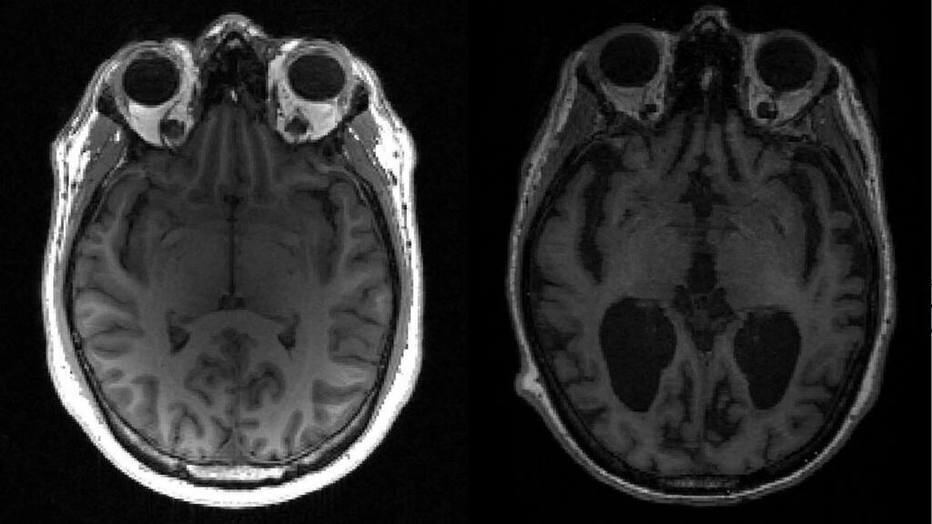

A doença de Alzheimer é uma doença neurodegenerativa, com maior probabilidade de atingir pessoas idosas. Ela é caracterizada pela perda das funções cognitivas como memória, orientação, atenção e linguagem. Até o momento, não há cura para Alzheimer. Existem tratamentos para controlar os sintomas e retardar o agravamento da degeneração cerebral típica da doença.